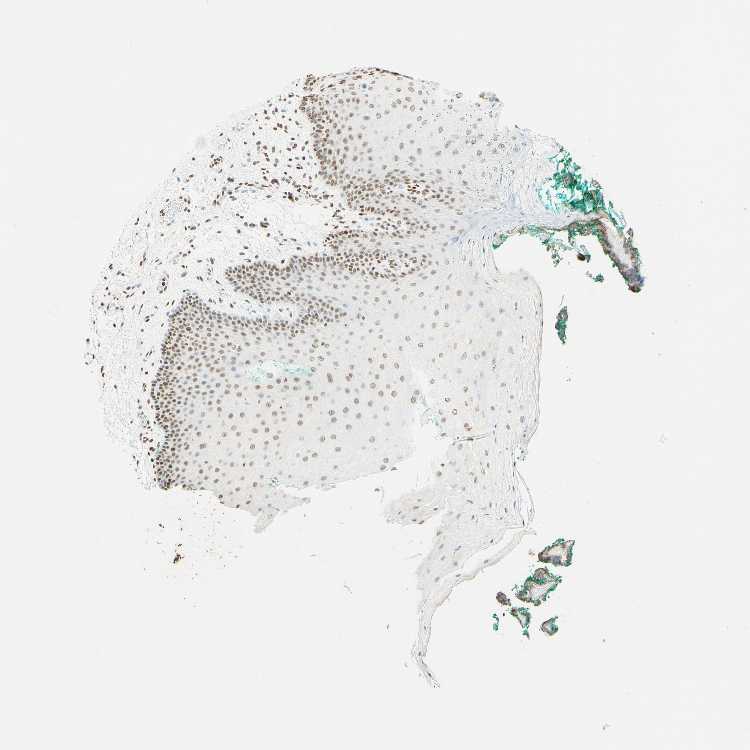

TISSUE PRIMARY DATA ORAL MUCOSA Show tissue menu

ORAL MUCOSA - Antibody stainingi

Antibody staining in the annotated cell types in the current human tissue is reported as not detected, low, medium, or high, based on conventional immunohistochemistry profiling in selected tissues. This score is based on the combination of the staining intensity and fraction of stained cells.

Each image is clickable and will lead to virtual microscopy that enables deeper exploration of all samples and also displays staining intensity scores, fraction scores and subcellular localization as well as patient and tissue information for each sample.

Antibody CAB009572Antibody CAB070867Antibody CAB080131

Squamous epithelial cells MediumHighHigh